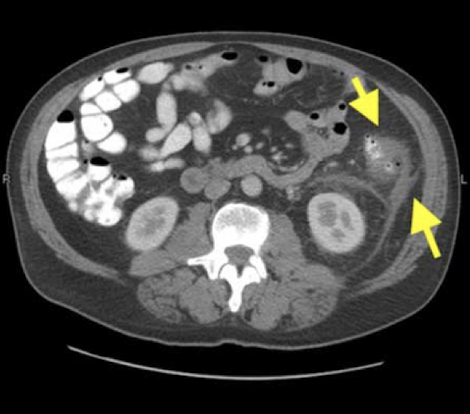

transverse

Which CT view?

Acute appendicitis

CT Abdomen/Pelvis IV contrast